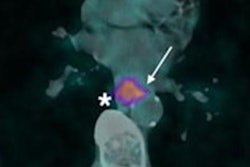

Ga-68 FAPI-PET/CT imaging in a 55-year-old male patient. No increased pulmonary tracer uptake was found (A, C). Tracer uptake colocalized with a sharply circumscribed, inhomogeneously contrast-enhancing mass on MRI without relevant diffusion restriction (B). Pathologic assessment diagnosed a tenosynovial giant cell tumor (D). Image courtesy of the Journal of Nuclear Medicine.Fibroblast activation protein (FAP) is overexpressed by cancer cells, and researchers suspect it is an essential component driving the growth of tumors. Experimental FAP-targeted molecular imaging radiotracers, such as FAPI-04 and FAPI-46, have shown promise in cancer research as well as for visualizing myocardial fibrosis.

Sellmann's team reported the rare tumor finding in a 55-year-old patient who underwent imaging due to persistent pulmonary symptoms after recovery from COVID-19. The patient was enrolled in a first-in-human trial testing Ga-68 FAPI-04 PET/CT scans (Biograph mCT, Siemens Healthineers) for identifying disease progression in 21 patients with interstitial lung disease.

The trial showed no increase in pulmonary radiotracer, but the researchers observed focally increased Ga-68 FAPI uptake in a mass in the patient's left thigh. Surgeons performed complete resection of the tumor.